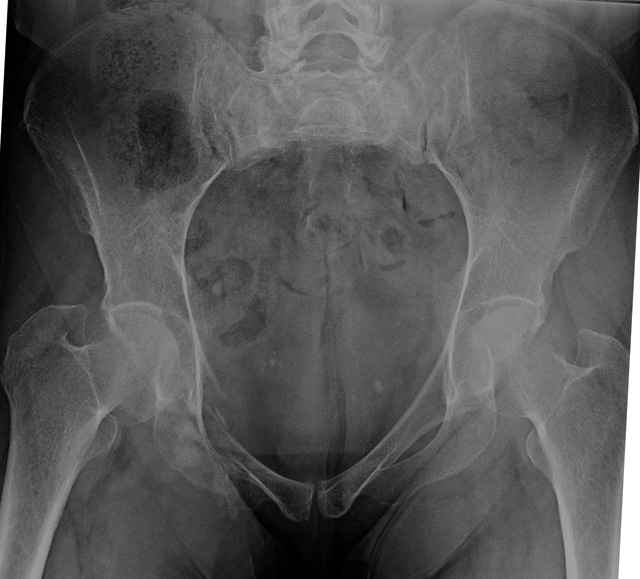

Here are a recent patient’s example slides...

54 yo Female Fell c/o Pain

3 Months After Fall

Continued Pain & Immobility

(+) Instability to Compressive Manual Exam

Sacral Injuries

Ramus Fractures